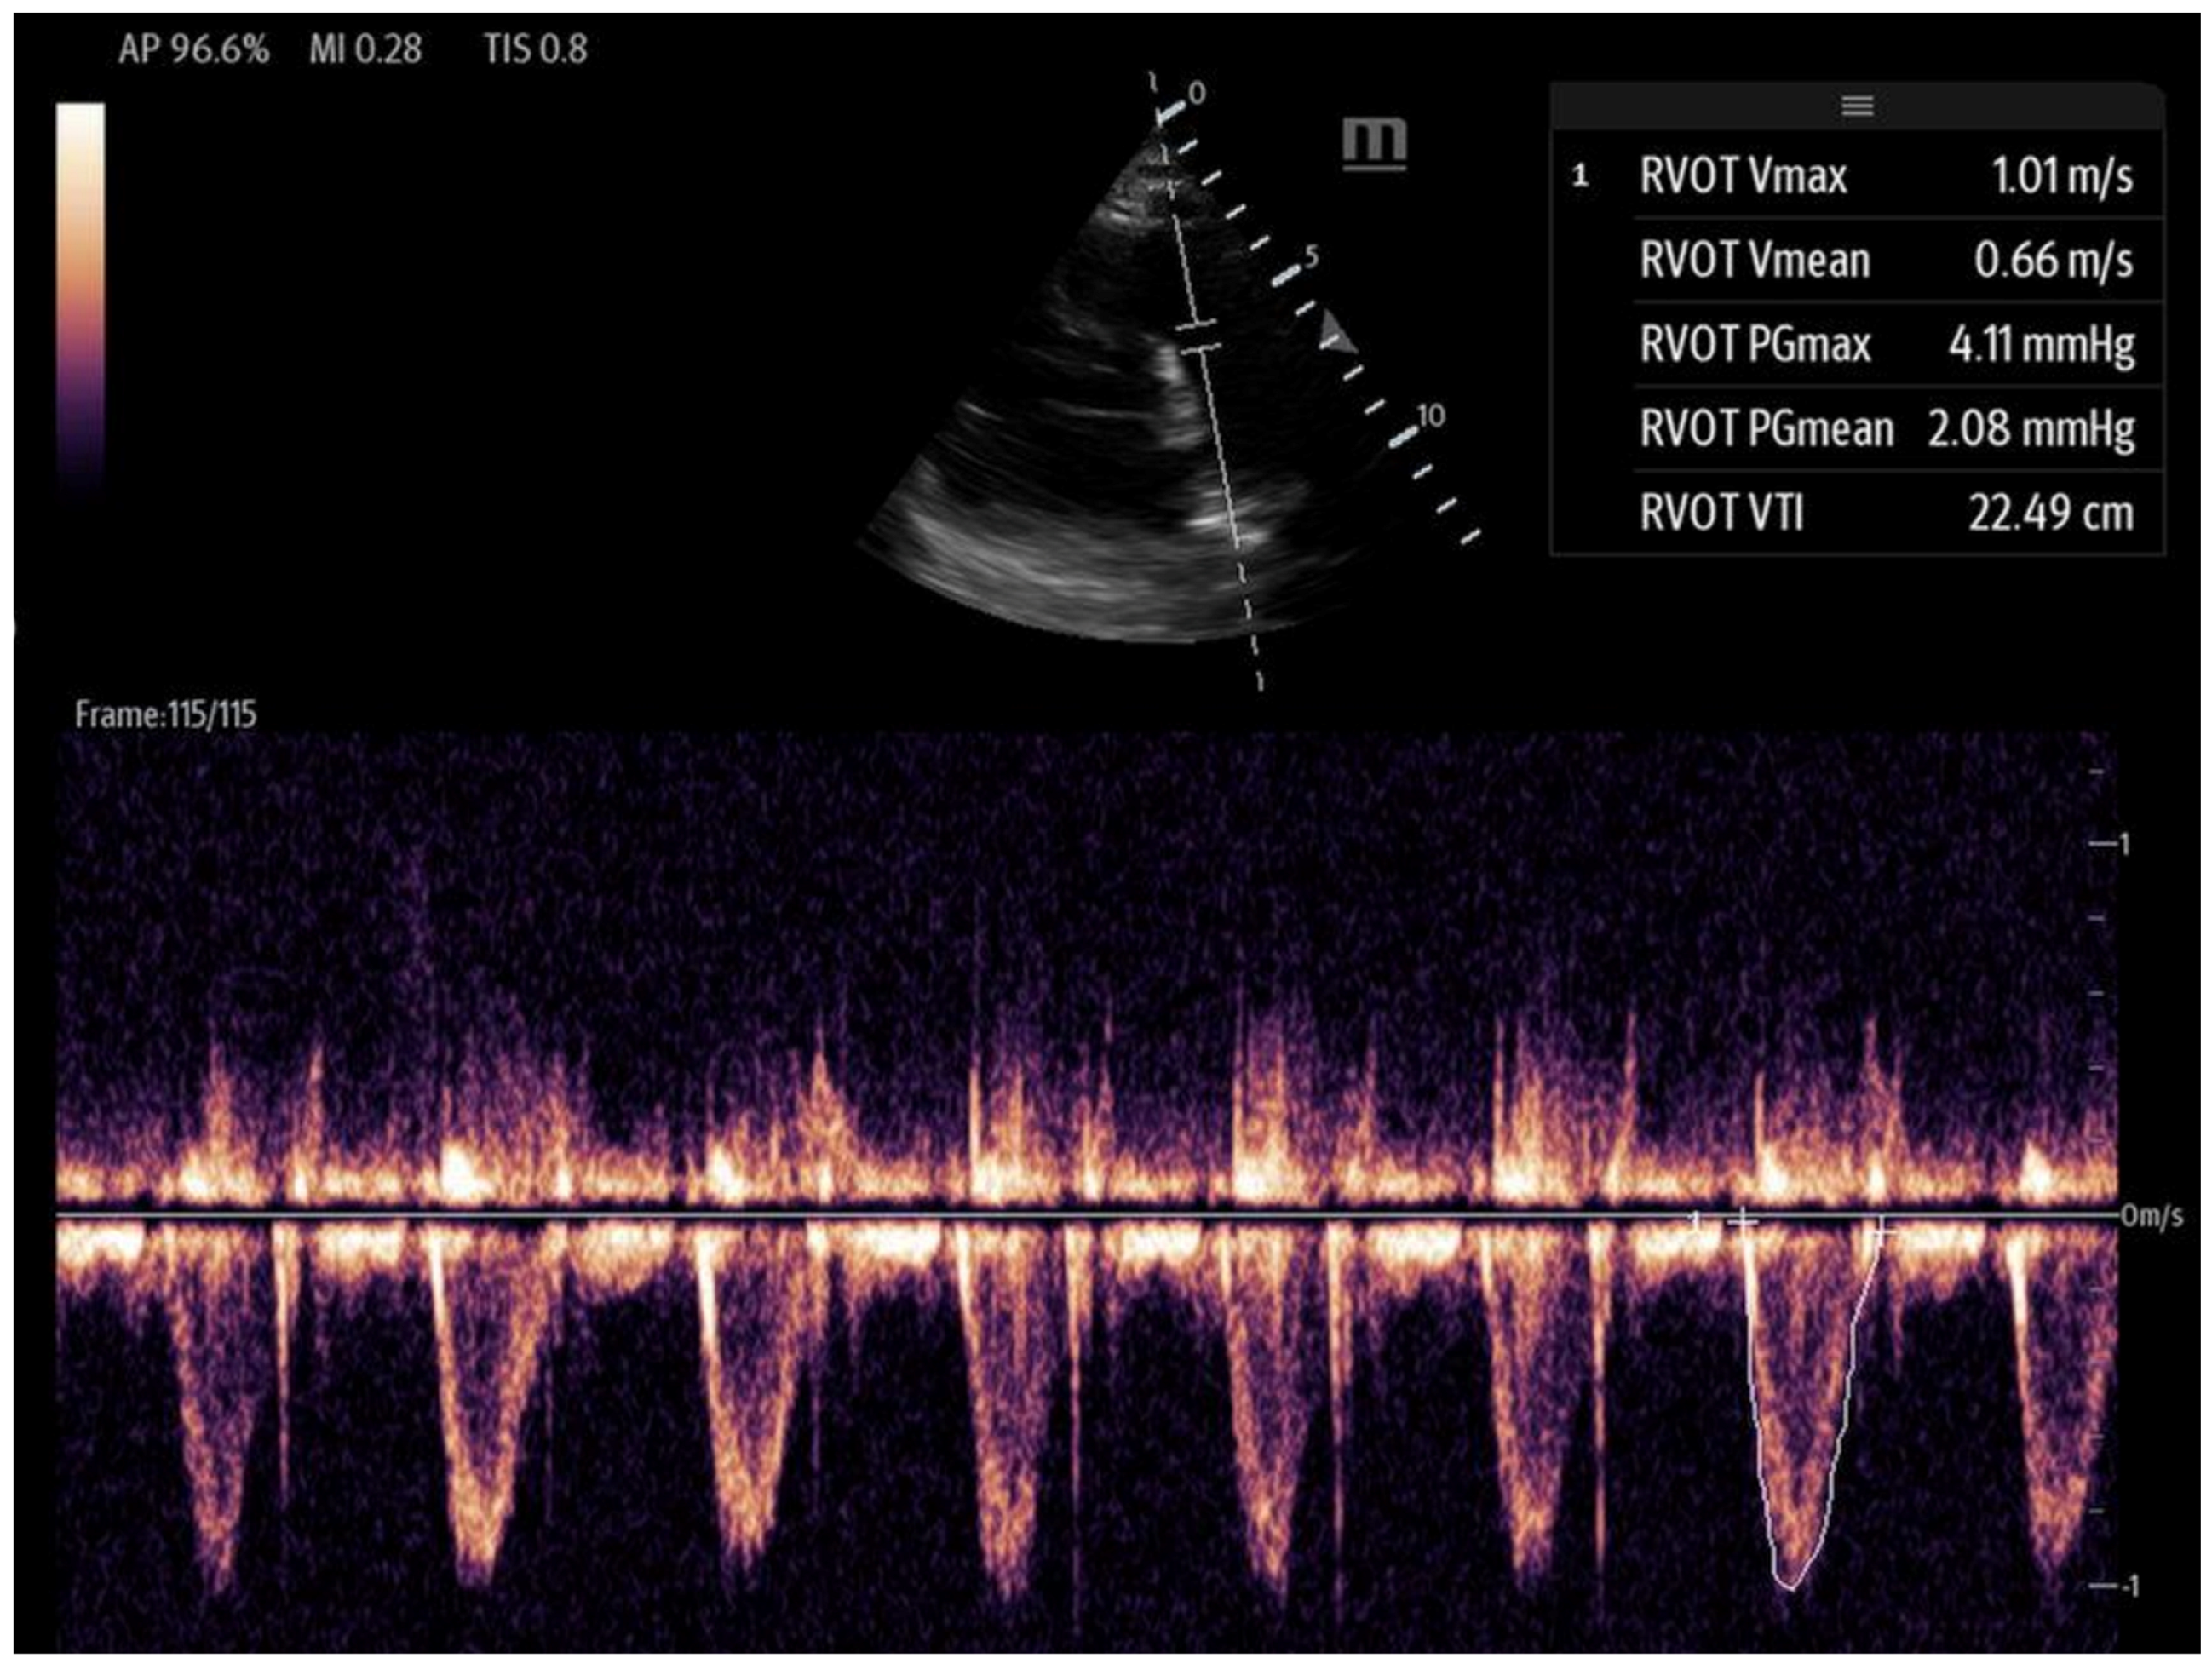

Figure 6. Tricuspid annular plane systolic excursion (TAPSE): apical 4-chamber view with M-mode activation, demonstrating reduced TAPSE (measured at the bottom 2D M-mode). - Right ventricular outflow tract velocity–time integral (RVOT-VTI): RV contractility can be evaluated using the RVOT-VTI, which represents the distance traveled by blood across the RVOT during systole. Stroke volume is calculated by multiplying the RVOT cross-sectional area by the RVOT-VTI. This measurement provides insight into both RV function and pulmonary vascular resistance, with an RVOT-VTI ≥ 12 cm considered normal [38] (Figure 7). The RVOT VTI is a better predictor of RV dysfunction in cardiogenic shock states compared to TAPSE and may also have prognostic value in patients with pulmonary hypertension [39,40].

Figure 7. A right ventricular tract VTI in a modified parasternal short axis view, activating the PW doppler. - Peak lateral tricuspid annular systolic velocity (S′ or systolic wave prime): S′ can be calculated by activating tissue Doppler imaging (TDI) at the lateral tricuspid annulus in the apical four-chamber view. An S′ velocity of less than 10 cm/s correlates strongly with RV systolic dysfunction and may even correlate better than TAPSE for normal RVEF to mild degrees of RVEF reduction. Specifically, an S′ < 11.5 cm/s correlates with an RVEF < 45%, with a sensitivity of 90% and a specificity of 85% [41]. The advantages of S′ include its ease and simplicity; however, similar to TAPSE, it is also limited by its one-dimensionality, as well as its load- and angle-dependence [36,42]. S′ alone is insufficient to capture regional wall motion abnormalities [36].